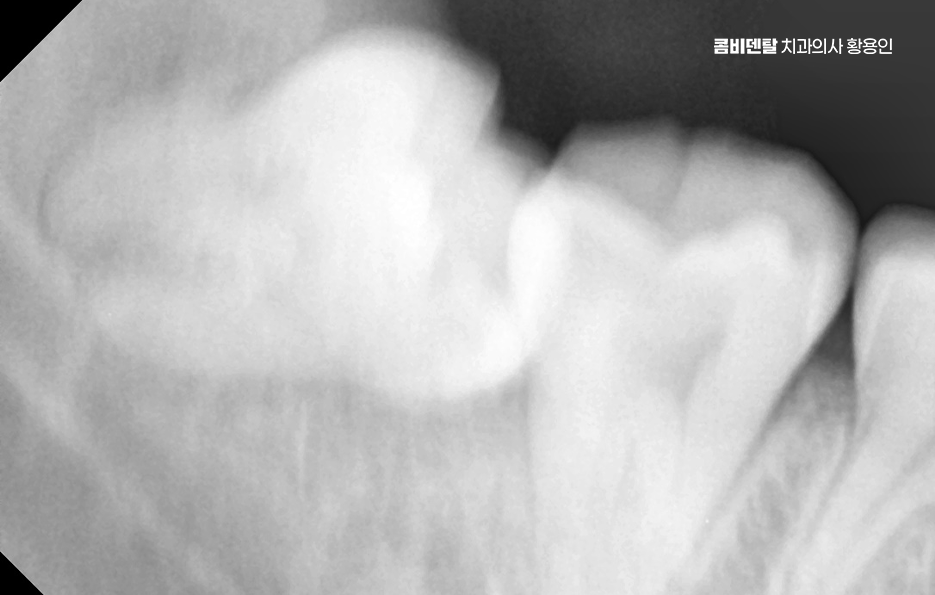

다시 말해 사랑니가 문제를 일으키는 건 워낙 흔한 일이지만 사랑니 하나만 문제를 일으키는 게 아니라, 그 옆 어금니까지 같이 충치가 생기는 경우도 생각보다 많은데 특히 아래쪽 사랑니가 옆으로 누워 있는 경우에는 그 앞 어금니와 밀착돼 있어서 둘 사이가 잘 닦이지 않고 음식물이 잘 끼기 쉬운 구조라고 할 수 있었어요.

문제는 여기서 끝나지 않고 누운 사랑니와 앞 어금니 사이에 충치가 동시에 생기는 경우는 치료가 더 복잡해질 수 밖에 없는데 왜냐면 사랑니가 옆으로 누워 있으니까 앞 어금니 뒷면에 생긴 충치를 제대로 보기도 어렵고, 치료 기구가 들어갈 공간도 부족해져서 충치 치료가 더 까다로워지는 것이며 특히 앞 어금니 뒷면에 생긴 충치는 환자도 자각하기 어렵고, 진단 시기도 늦어지는 경우가 많아서 이미 신경까지 손상됐거나 신경치료가 필요한 상태로 발견되는 일도 많이 있었어요

사랑니 발치 후 충치 치료 이런 경우, 사랑니를 발치하지 않은 채로 어금니 충치 치료만 한다면 문제는 해결되지도 않고 사실상 치료적 접근도 어렵기 때문에 사랑니가 원인이 되어 어금니 충치가 생겼다면, 먼저 사랑니를 발치하고 나서 어금니를 치료하는 순서가 맞는 거예요.

또 하나 중요한 점은, 사랑니를 발치한 후 생긴 공간이 오히려 어금니 충치 치료를 더 수월하게 만들어 준다는 점으로 사랑니가 있을 때는 치료 기구 접근이 힘들었지만, 발치 후에는 시야가 확보되면서 어금니 치료가 더 깔끔하고 정확하게 가능해질 수 있어요